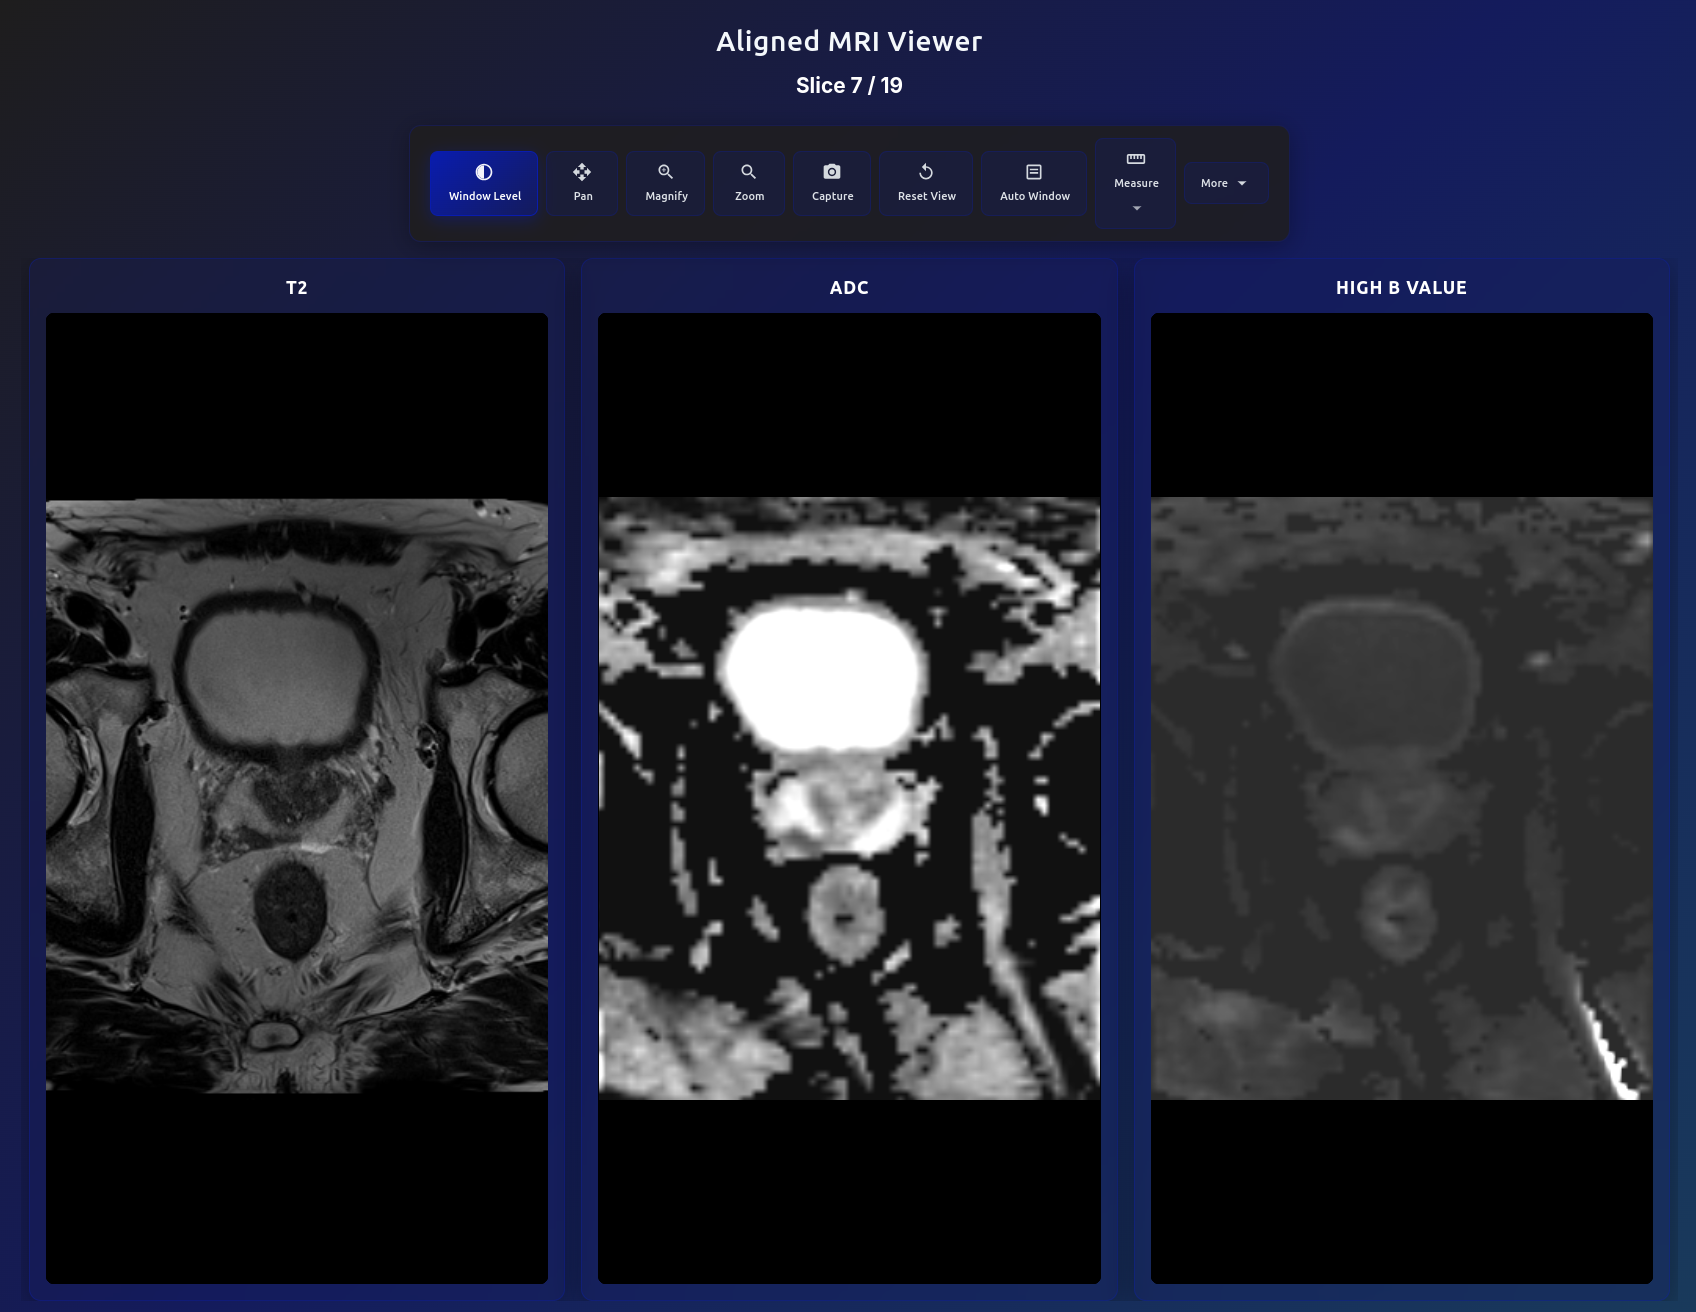

Aligned MRI viewer showing T2, ADC, and High B Value in same voxel space

Automated Image Alignment

All biparametric series (T2, ADC, high b-value) are automatically registered into the same voxel space using affine alignment. Scroll through any slice and all three sequences stay perfectly synchronized — enabling direct visual comparison of signal characteristics across modalities.